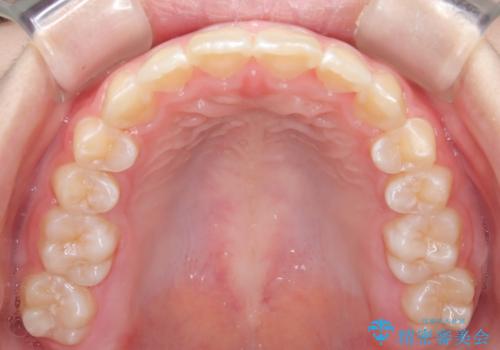

- 前歯が出ていることを主訴に来院されました。

インビザラインにて奥歯の遠心移動を行いながら最大限前歯が下がるように治療を行いました。

今回は遠心移動とIPRによってここまで前歯を下げることができました。